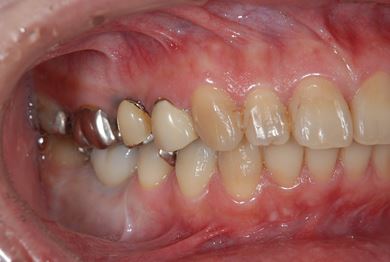

インプラントの症例写真 IMPLANT

骨再生インプラント治療

| 性別/年齢 | 女性 / 46歳 | ||||||||||||||||||||||||||||||||

| 主訴 | 歯ぐきがただれてる。歯が少しうずく。 | ||||||||||||||||||||||||||||||||

| 治療方針 | インプラント治療にて、機能的・審美的回復を行う。 | ||||||||||||||||||||||||||||||||

| 治療内容 | インプラント1本(GBR)、ハイブリッドセラミック1本 | ||||||||||||||||||||||||||||||||

| 総治療費 | 368,655円 | ||||||||||||||||||||||||||||||||

| 治療期間 | 7ヶ月 |